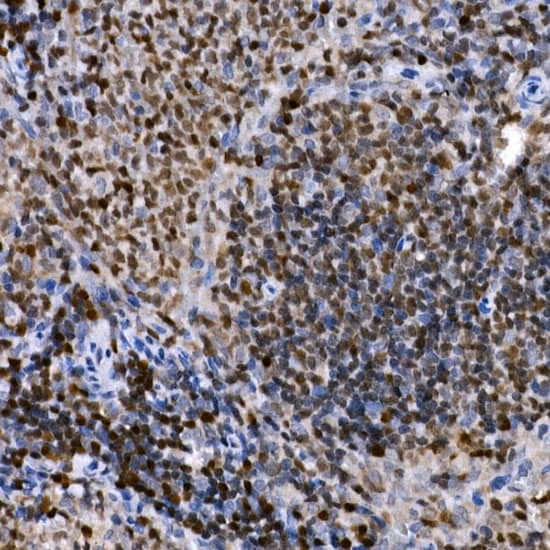

Supportive validation

- Submitted by

- Invitrogen Antibodies (provider)

- Main image

- Experimental details

- Immunohistochemistry analysis of PHF11 in paraffin-embedded rat spleen. Samples were incubated with PHF11 Polyclonal antibody (Product # PA5-89229) using a dilution of 1:50 (40x lens). Perform high pressure antigen retrieval with 10 mM citrate buffer pH 6.0 before commencing with IHC staining protocol.